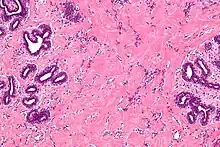

High magnification micrograph of pseudoangiomatous stromal hyperplasia showing the characteristic small, anastomosing blood vessel-like channels. H&E stain.

Pseudoangiomatous stromal hyperplasia (PASH) is an overgrowth of myofibroblastic cells in the breast. It has an appearance similar to fibroadenomatoid changes.[1]